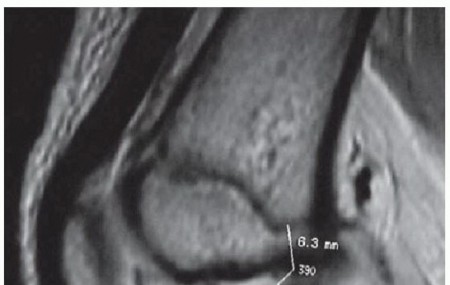

Osteochondritis Dissecans and Large Osteochondral Defects of the Knee DEFINITION Osteochondritis dissecans (O…